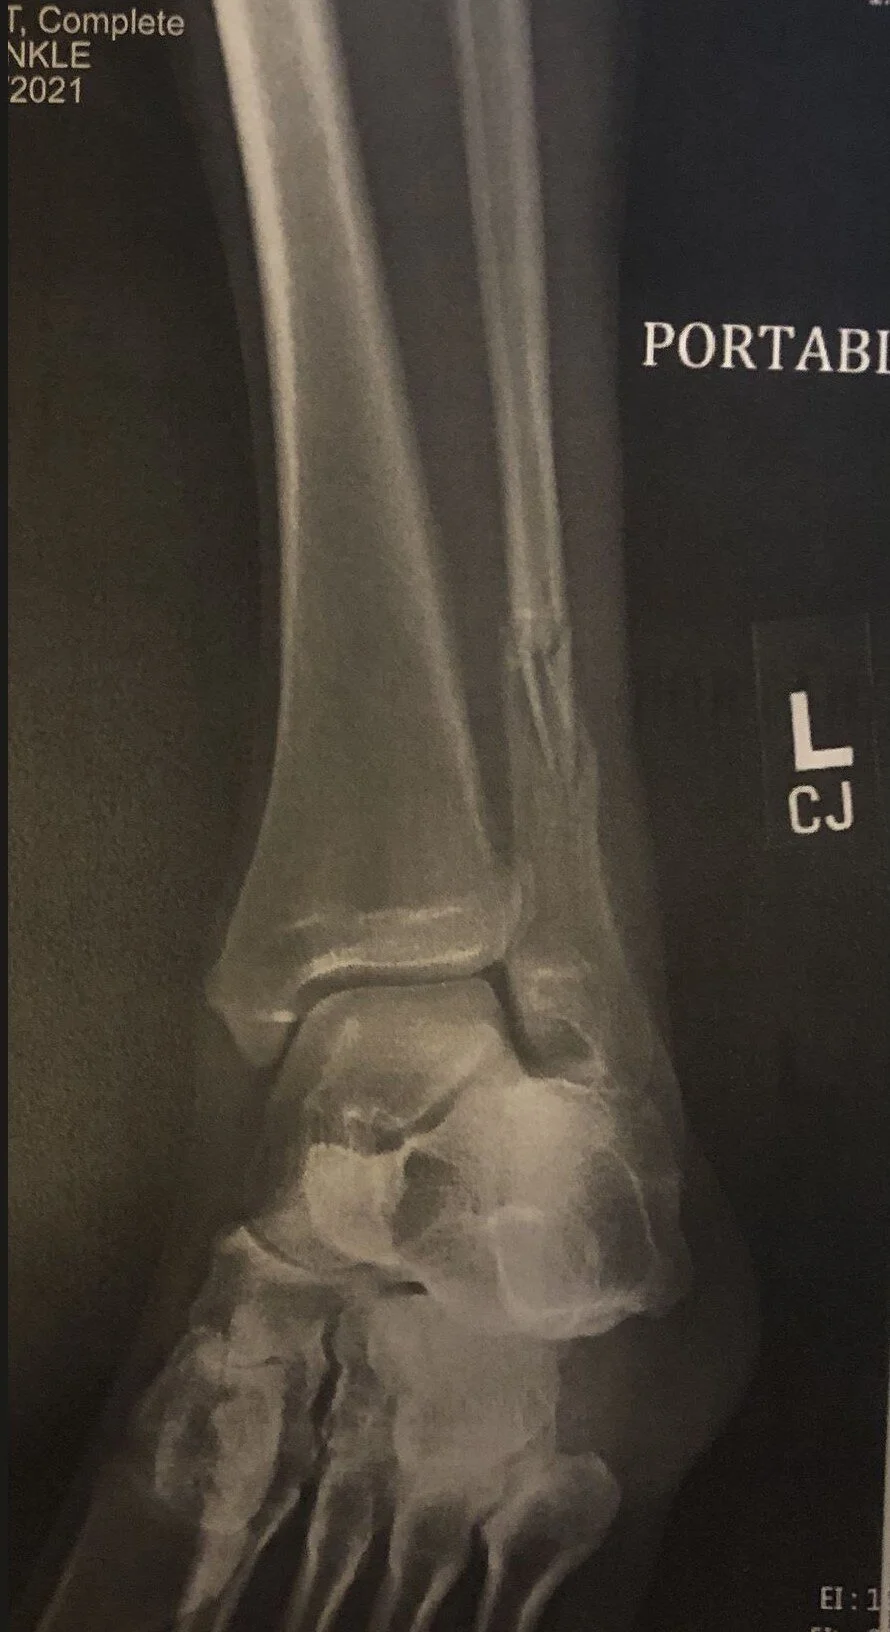

When the 2005 Pontiac Grand Prix hit me from behind, it knocked off the vehicle’s passenger-side mirror and a piece of trim. More personal, enduring evidence is found in my fractured back, the contusions on my concussed head, and the broken fibula. These serve as reminders of what I otherwise cannot recall, the painful evidence of the violence done to me.

Fractured Fibula 03.13.21.jpg

I know all the ways it’s necessary to have a contract tow company pick up vehicles from crash scenes and I am not so naïve as to think these charges are anything other than part of the deal to get this service performed. But it seems possible to have a more generous, common-sensical approach to keep those who have been nearly killed – whether on a bicycle or behind the wheel – from having to pay to get their rides back. I focus on this small injustice precisely because I can be reasonable about it. Other injustices of this crash are too big to contemplate, much less maintain a reasoned equilibrium.